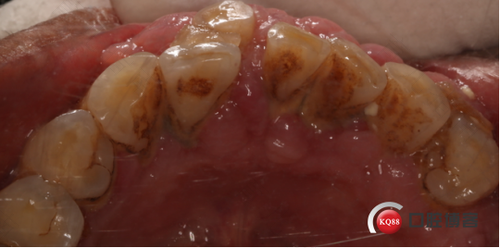

2、对于口腔卫生不良引起的牙龈增生,食物残渣滞留在龈沟内,经细菌作用形成牙石。或者牙龈充血,红肿增生而形成的炎症性增生等等。只要清除掉污物,保持日常口腔卫生,定时做好口腔清理,做好清洁工作,就可恢复正常。当然,选取正确的清理方式也十分重要。